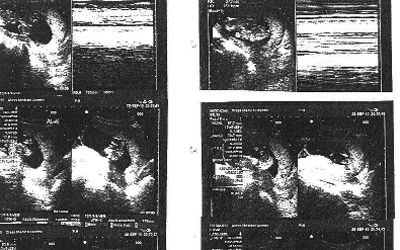

وقال (أبويمان) لـ«الإمارات اليوم»، إن «ولادة التوائم الثلاثة ستتم في مستشفى القاسمي في الشارقة، كون المستشفى يعد أحد أفضل المستشفيات في عمليات الولادة، كما أن مصاريف الولادة غير مبالغ فيها»، لافتاً إلى أن «تكلفة العملية القيصرية لا تتجاوز 4000 درهم غير شاملة اقامة الأم والتي تكلف 100 درهم عن كل يوم، إضافة إلى 100 درهم عن اقامة كل طفل في الحاضنة بعد الشهر الثاني، لاسيما أن الشهر الأول مجاني». وذكر أن «موعد ولادة التوائم سيتحدد الأسبوع المقبل، بعد انتهاء الشهر السادس من حمل زوجته.